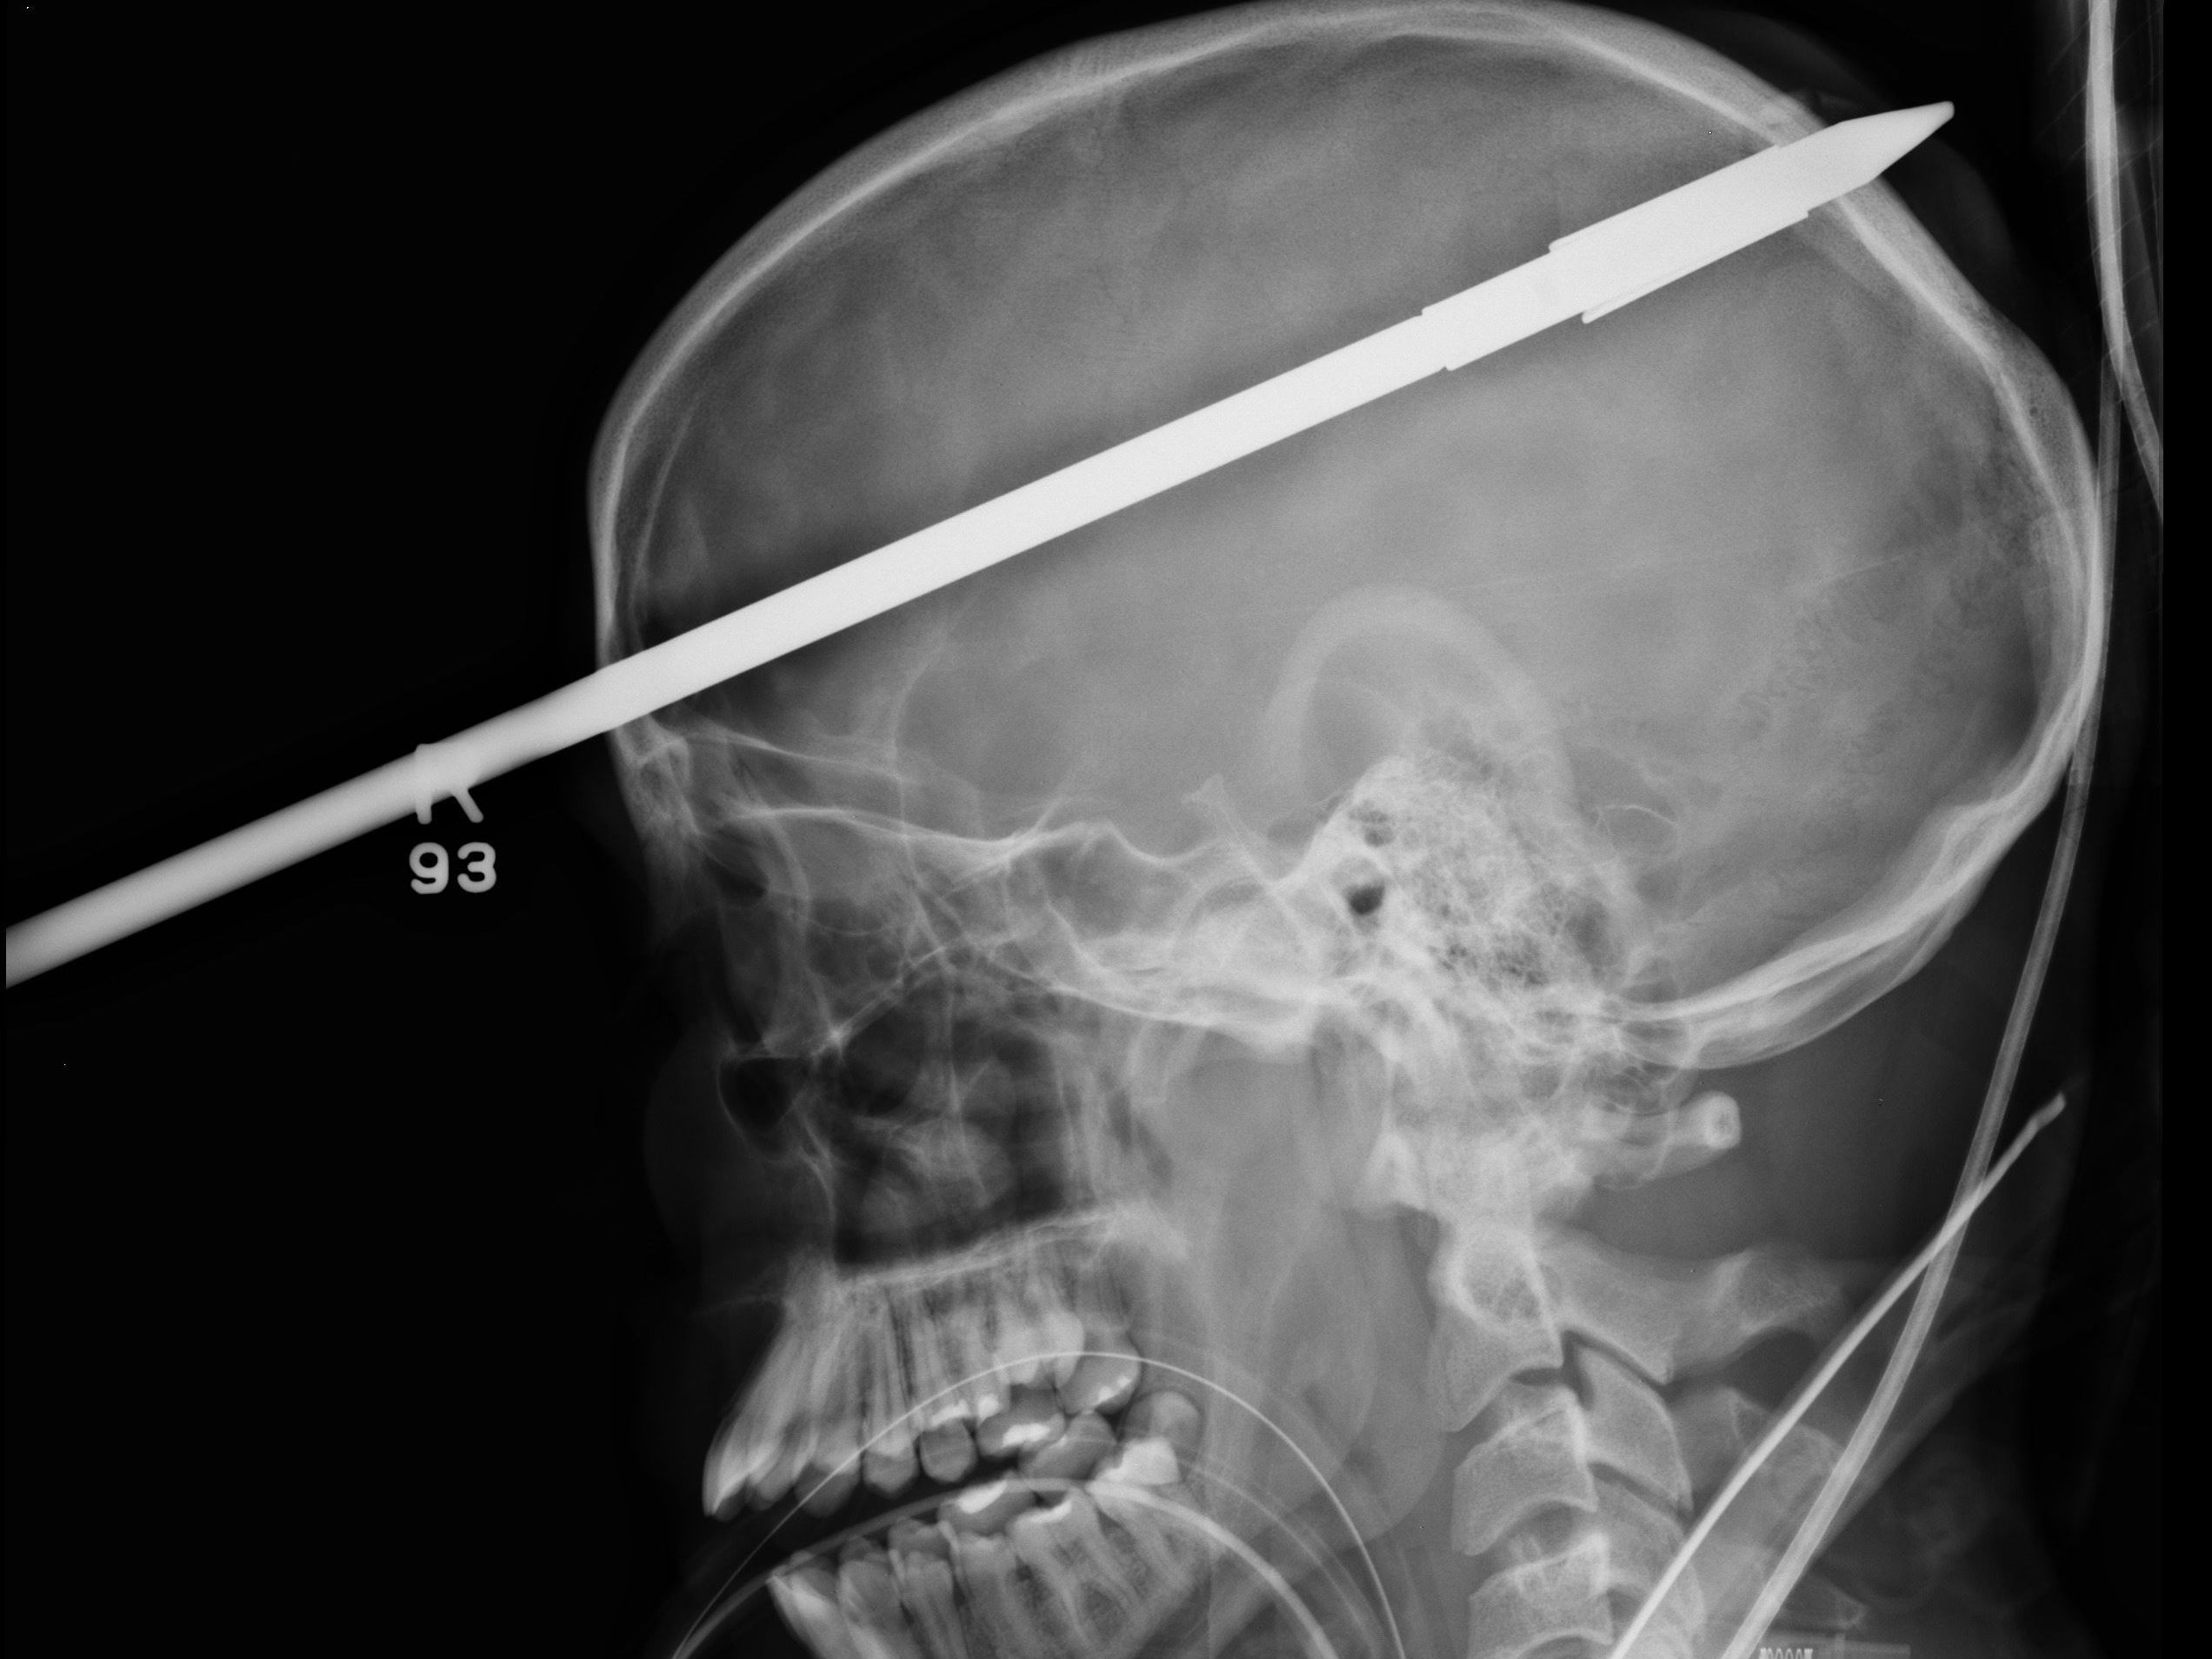

Der Pfeil ist fünf Zentimeter über rechtem Auge ein- und am Scheitel wieder ausgetreten.

Er entging nur knapp der Erblindung: Der spitze Pfeil trat fünf Zentimeter über seinem rechten Auge ein und am Scheitel wieder aus. Ärzte des Jackson Memorial Hospital in Miami (Florida) konnten die Harpune Anfang Juni in einer riskanten, dreistündigen Operation entfernen.

91 Zentimeter des Speers hatten aus dem Kopf des Patienten herausgeragt. Bevor eine Röntgenaufnahme gemacht werden konnte, wurde der Speer mit Hilfe eines Bolzenschneiders auf 45 Zentimeter verkleinert. Erinnern kann sich der Jugendliche an den Unfall nicht. Die nächsten zwei bis drei Monate wird er im Krankenhaus verbringen.